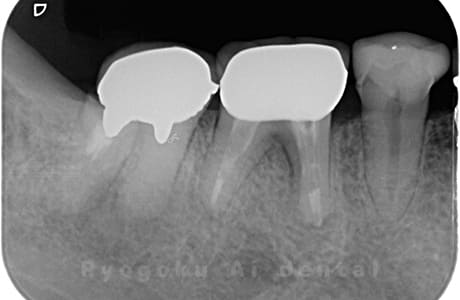

Case07

-

- 原因

- 右下6番歯根破折

- 治療内容

- インプラント治療

- 治療費用

- 約600,000円

右下の腫れが治らないとの事でご来院された患者様です。歯が割れていたため、抜歯を行い、骨に代わるお薬を入れ、インプラントを埋入致しました。経過良好で大変満足していただけました。

<リスク・副作用>

治療後、痛みや違和感、出血、腫れなどが出る事があります。喫煙者、糖尿病などの方の場合、歯が生着しない場合があります。